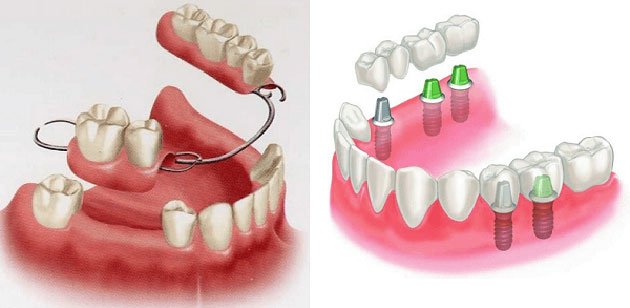

- Dental Implant – Have teeth for chewing after 48 hours